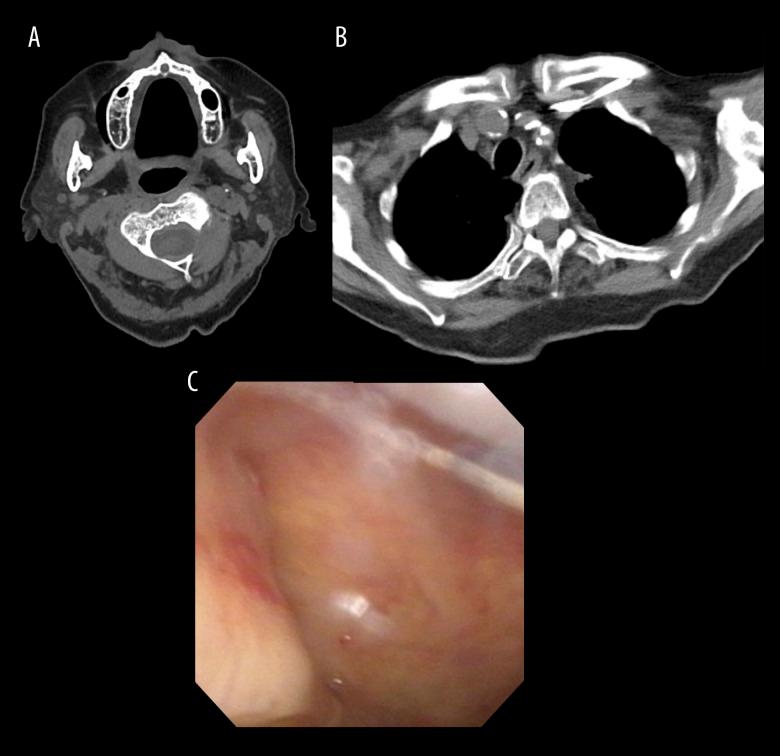

BACKGROUND The nasogastric tube (NGT) is a common medical device, and serious complications associated with NGT insertions are rare. The most common serious complication is tracheal insertion; cervical emphysema and pneumomediastinum are rare. There are several methods for confirming the location of the NGT, but a single method of confirmation is often inadequate. Confirmation by air insufflation into the NGT is currently not recommended and is highly invasive. Here, we report a case of cervical emphysema and pneumomediastinum caused by an NGT. CASE REPORT A 94-year-old woman experienced a stroke and was hospitalized for neurosurgery. The nurse inserted an NGT and performed insufflation, but air sounds were not detected. Chest radiography did not reveal the tip of the NGT. Computed tomography (CT) revealed cervical emphysema, pneumomediastinum, an NGT bent in the esophagus, and the distal end of the NGT in the nasopharynx. Nasopharyngeal endoscopy revealed damaged nasopharyngeal mucosa and the distal end of the NGT. The patient was diagnosed with insufflated air passing through the damaged nasopharynx, which had spread to the cervical area and mediastinum. The NGT was removed, and the patient was treated with antibiotics. CT showed cervical emphysema, and the pneumomediastinum resolved after 20 days. CONCLUSIONS It is important to recognize that there are numerous serious and unexpected complications associated with NGT. Different methods should be considered and used to confirm the location of an NGT. Further studies on the confirmation methods and dissemination of such knowledge are required to reduce NGT complications.

一名 94 岁女性因中风住院接受神经外科治疗。护士插入了一根 NGT 并进行了充气,但未听到空气声。胸部 X 光片未显示 NGT 的尖端。计算机断层扫描(CT)显示颈气肿、纵隔气肿、NGT 在食管中弯曲以及 NGT 的远端在鼻咽部。鼻咽喉镜检查显示鼻咽部黏膜受损和 NGT 的远端。患者被诊断为充气的空气通过受损的鼻咽部扩散到颈部和纵隔。NGT 被取出,患者接受了抗生素治疗。CT 显示颈气肿,20 天后纵隔气肿消退。